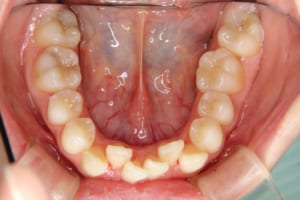

治療前

主訴 下の歯の凸凹

上の前歯が出ているのが気になる

その他/備考 上顎右側中切歯および側切歯が、埋伏していた犬歯によって歯根吸収していました。